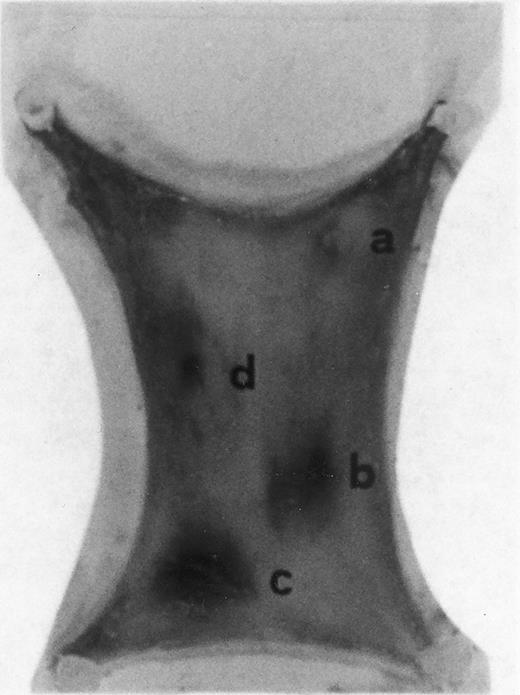

Evan's blue-stained intradermal injection sites showing the kinetics of the dermal response to exogenous human RANTES 10 ng/50 μL (c) and MCP-1 10 ng/50 μL (d); while (a) is a negative control (PBS 50 μL) and (b) is a positive control (FMLP 10−6 mol/L in 50 μL). This representative experiment was found to be reproducible and has been performed at least three times.

Intradermal injection sites of chemokines RANTES and MCP-1.In order to assess the inflammatory activities of RANTES and MCP-1 in an in vivo model we have injected 50 μL of these chemokines in four distinct sites of the abdomen of rats for the duration of 4 hours. At this time point animals were killed in accordance with previous data indicating that 4 hours is the optimal time for chemokine-induced chemoattraction.23-26 RANTES and MCP-1 were used at 10 ng/50 μL; while the chemoattractant peptide FMLP was used at 10−6 mol/L.8 In Fig 1 PBS (a, negative control) was not effective in promoting inflammation; RANTES at 10 ng/50 μL (c) enhanced dye extravasation at a greater extent than FMLP 10−6 mol/L (b, positive control); while MCP-1 at 10 ng/50 μL (d) was less effective than FMLP. In Table 1 we report a representative experiment with 12 treated rats. After chemokine challenge (4 hours) we calculated the mean ± S.D. of the major diameters (in mm) of dye extravasation at the site of injections (4 rats). Reported P values were obtained by comparing the effect of RANTES to MCP-1.

The size of the inflamed areas treated with RANTES (10-20 ng/50 μL) were significantly larger when compared with MCP-1 (10-20 ng/50 μL) and FMLP (10−6 mol/L) (50 μL)-treated areas (Table 1). However, in LPS treatment, larger dye extravasation areas were produced than those observed with RANTES at either concentrations of 10 or 20 ng/50 μL. Maximum dye extravasation was obtained with LPS (84.6 mm ± 10, 10 ng/50 μL) and RANTES treatments (70.52 ± 12, 20 ng/50 μL). When H1 or H2 blockers were used to exclude the possible involvement of basophilic cell degranulation, the inflammatory effect of RANTES and MCP-1 was not changed.31